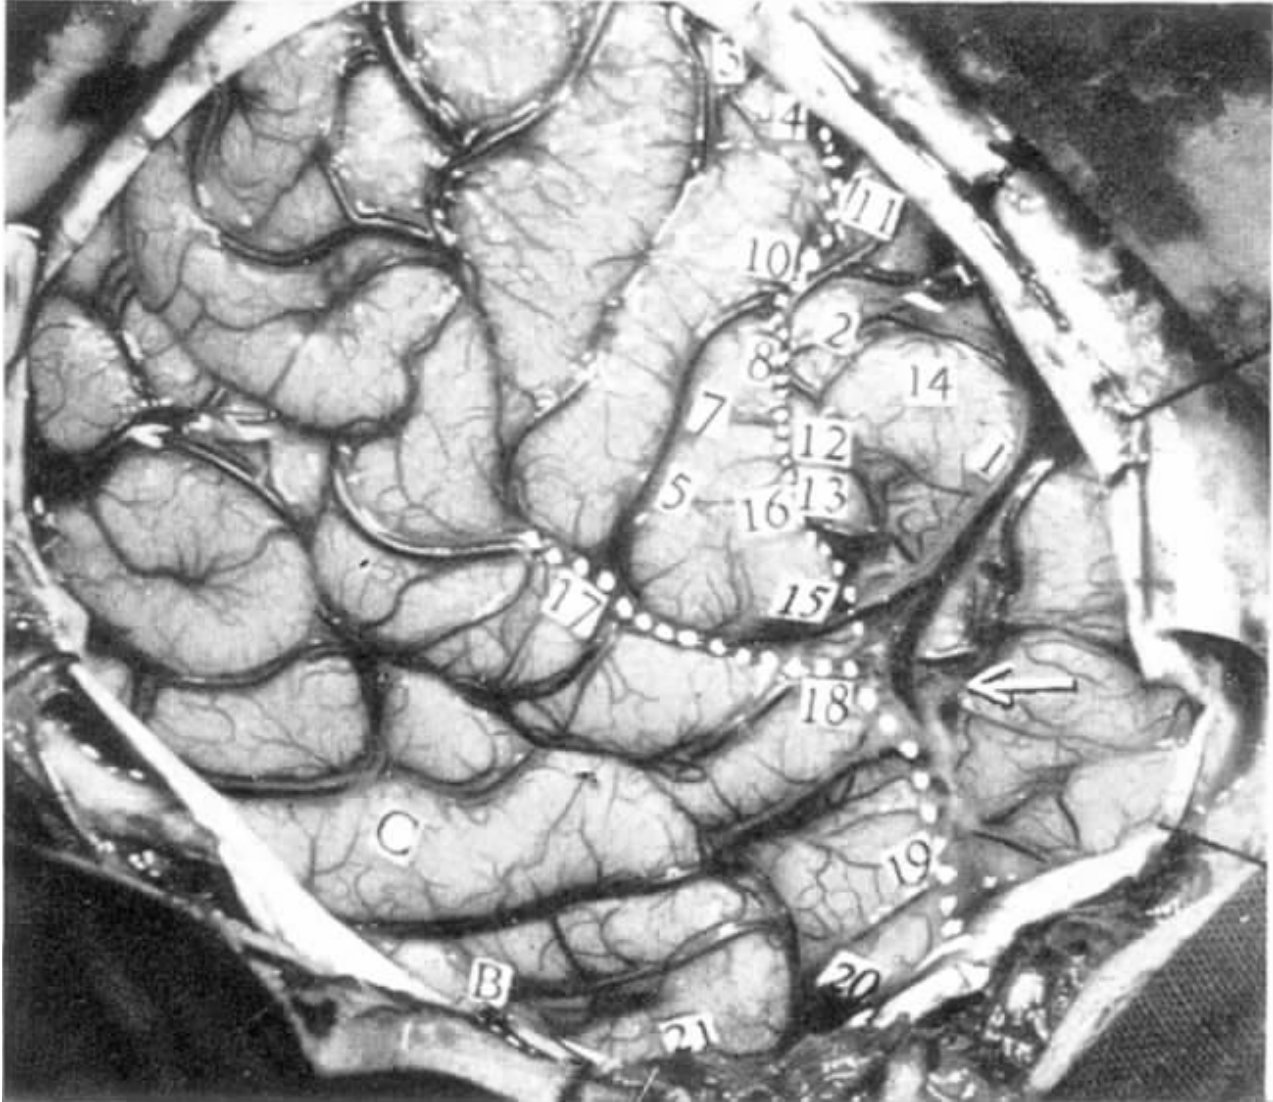

26岁,男性。出生时大脑受过伤,左侧中央沟后区是损伤最严重的部位(损伤范围见图4-1),他的外侧裂也向上移动了相当的距离。左利手。右侧面颊出现麻木感是癫痫发作的先兆。

左脑,近中央沟处的运动区,次级感觉区和次级运动区(见图4-1)。

图4-1 病例H.Fa.刺激点与所引起的反应

电刺激脑的反应及特点

刺激条件:拉姆刺激仪,频率为60Hz,电压是1V,1.5V和2V。没有发作后放电。

20 “我手臂没有力气。”患者后来说,“我感觉好像失去了它,就像它不知不觉溜掉了一样。”让患者挤压麻醉师尼尔的双手。在无提醒的情况下进行刺激,这导致他右手挤压的力量突然减低,尽管他的左手仍继续施压。但在刺激结束时,右手挤压力突然又产生。

18 “右手出现奇怪的感觉,有移动的趋势。我相信它确实动了。”能观察到那只手手指轻微伸展。

18 重复刺激并要求患者保持手不动。这次手指没有运动。

18 要求患者双手互握。在随后的刺激过程中,他的右手几乎完全变松弛。但电极一撤除,他的右手又恢复握力。

20&18 皮层电位显示皮层活动抑制。其后各个电极依次产生慢波。

15 患者嘀咕着:“我双侧手脚都有感觉。这种感觉起始于脸部,可能主要是右脸。”当要求患者描述他的感觉时,他说:“那是种麻木的感觉,我的脚好像要抬起来。”

35 “我的右脚有轻微的感觉,似乎要将脚弓抬起来了。”

35 在病人的右脚做随意运动时重复刺激,运动没有被打断。很显然,他这次没有任何感觉。

33 肩膀和双手有感觉,主要是右侧。

12 脸部有感觉,他描述为围绕着嘴唇,在右侧。

12 一段时间间隔后,在无提醒的情况下重复刺激。他的右侧脸有感觉,可能也包括左脸,并向下延伸到躯体。

12 无提醒的情况下重复刺激,同时让患者用双手互握。刺激过程中,右手的力量明显下降。在刺激结束后,尼尔博士一声惊叫,因为他感到患者右手突然发力。

14 左脸有感觉,同侧身体也有轻微的感觉。

●该病例有脑回变形和移位的现象,这在产伤患儿的头部发育过程中经常发生。

●被称为次级感觉区的区域似乎位于中央前回向下延伸处,而产生感觉的部位包括身体两侧,对侧稍强。感觉包括麻木感和该部位好像要朝特定方向的移动。

●刺激点20的运动效果与刺激次级感觉区的效果相似。有一种要失去它的感觉,而且毫无疑问,对侧手臂随意动作麻痹与电位抑制相关。这种抑制作用在刺激撤除后便立即消失。对相邻的点12的刺激造成随意动作的力度降低,但不会麻痹。

●本病例有两个现象与随意运动系统有关:一是运动感觉或是一个部位即将要运动的感觉,二是对随意运动的抑制。

本例主要是对患者左脑,近中央沟处的运动区,次级感觉区和次级运动区进行刺激。引起的反应主要包括:对对侧肢体随意运动的抑制,麻木感和该部位好像要朝特定方向移动的感觉。